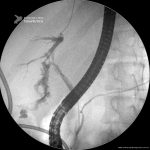

Fístula Biliar

- Imagem da radioscopia mostrando fístula biliar pós-colecistectomia, com identificação de extravazamento de contraste na região do hepatocolédoco médio-proximal.